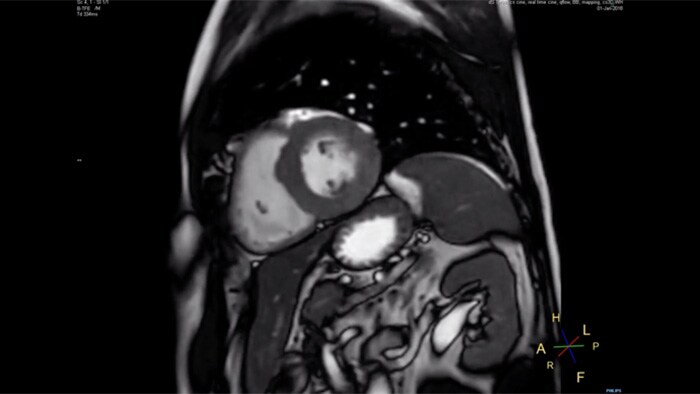

4.8 sec breath hold time

Since short breath hold times make it easier for our patients to comply, the failure of breath holding largely disappeared.

At our facility, we found in Cardiac MR fewer breath holds are now needed, or breath hold times are shortened."

Dr. Takashi Koyama, MD, PhD, Diagnostic Radiologist and Director of the Department of Radiology Center and Diagnostic Radiology, Kurashiki Central Hospital, Japan

A 15- or 16-second breath-hold is tough for many cardiac patients. With Compressed SENSE we actually have protocols now that can get that below 10 seconds. It’s a lot easier to get through for a patient, and patients are a lot more satisfied with the experience.”